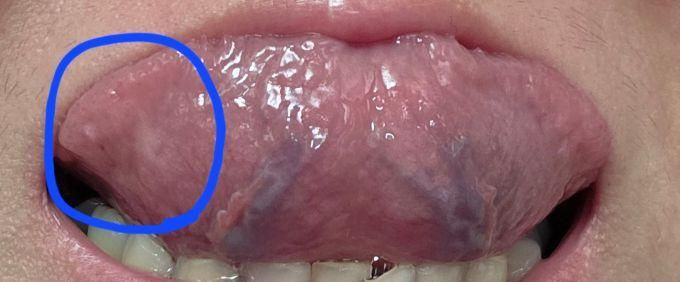

혀밑에 하얀 이거 설암증상인 백색반점인가요??ㅠㅠ

(사진을 크게해서 보시면 파란색으로 동그라미 친부분입니다 사진이 커서 한번에 안보이네요)

근데 오늘아침보니까 혀 밑이 저렇게 하얗게 됐어요

인터넷 찾아보니 무서운얘기들뿐인데 설암증상중에 하얀반점같은게 생기면 설암일수 있다던데

제 혀밑에 하얀게 혹시 그런건가요?

설암 같은 것은 아닙니다. 단순히 혀가 치아면에 압박을 받아 생긴 단순염증입니다. 그냥두면 저절로 좋아집니다.

사진상으로 보면 문제가 잇는건 아니고 정상정인 혀 같습니다 .큰 문제가 잇어 보이진 않습니다 단순히 쓸려서 통증이 잇는거 같습니다.

1. 백색 반점이 전암 병소일 수는 있으나 사진상으론 공격적인 양상으로 보이진 않고요

2. 구강내과가서 한번 조직검사 받아보세요